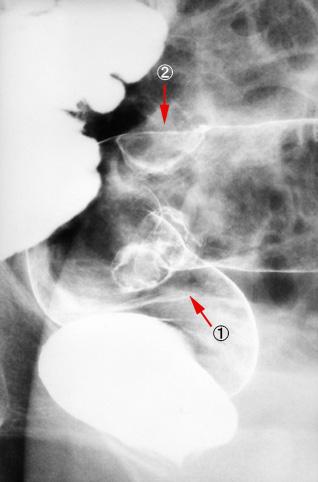

疾患(病理主体)の分類悪性上皮性腫瘍/腺癌

部位(臓器別)大腸/直腸

検査方法X-P

腫瘍の肉眼分類2型(潰瘍限局型)/

病変の最大径(ミリ)25〜29

腫瘍の深達度mp

多発腫瘍(同一臓器)有(同時性)